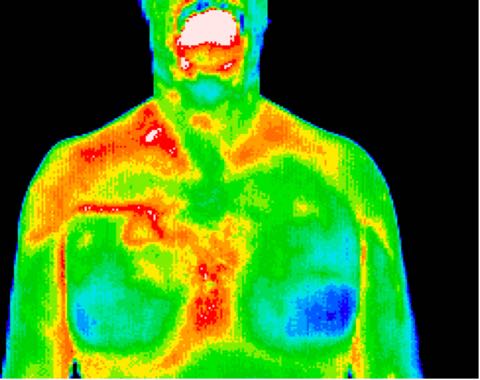

Breast screening

1% of breast cancers are in men